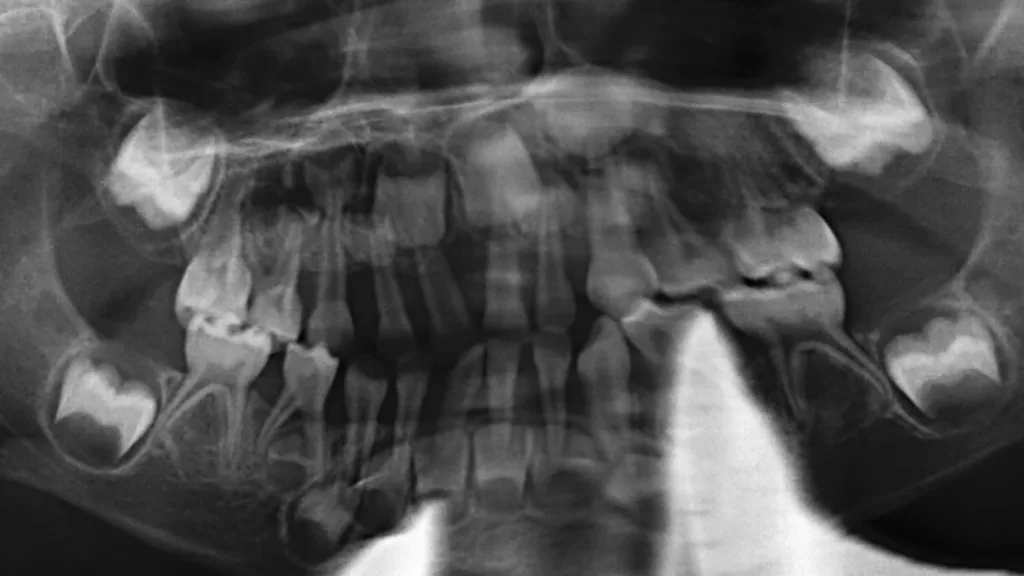

Im Gegensatz dazu existieren eine Reihe seltener Syndrome, bei denen betroffene Personen unabhängig von klassischen Risikofaktoren eine schwere parodontale Destruktion entwickeln. Seltene Syndrome sind (meist) genetisch bedingte Erkrankungen, die durch eine charakteristische Kombination klinischer Symptome gekennzeichnet sind und gemäß europäischer Definition eine Prävalenz von weniger als 1 pro 2.000 Personen aufweisen. In der Parodontologie ist eines der bekanntesten Beispiele das autosomal-rezessiv vererbte Papillon-Lefèvre-Syndrom, das durch eine rasch-progrediente Parodontitis im Kindesalter sowie durch palmoplantare Hyperkeratosen der Hände und Füße gekennzeichnet ist; ursächlich sind Mutationen im Cathepsin-C-(CTSC-)Gen (Abb. 1, Abb. 2).

Primäre Immundefizienzen bilden die größte Gruppe an Syndromen, die sich mit einer Parodontitis manifestieren. Diese genetisch heterogenen Erkrankungen beeinträchtigen die Struktur, Reifung, Differenzierung oder Funktion von Organen und Zellen des Immunsystems. Sie werden typischerweise durch pathogene Veränderungen einzelner Gene – sogenannte monogene Mutationen – verursacht. Innerhalb dieser Gruppe sind insbesondere angeborene Störungen in Zahl und Funktion neutrophiler Granulozyten mit Parodontitis assoziiert. Typische Beispiele hierfür sind schwere kongenitale Neutropenien (Abb. 3, Abb. 4) und das Papillon-Lefèvre-Syndrom. Andere Syndrome, wie das Hermansky-Pudlak-Syndrom oder das Chediak-Higashi-Syndrom, resultieren aus Funktionsstörungen lysosomenassoziierter Organellen, die für die normale Aktivität zahlreicher Immunzellen essenziell sind, während wieder andere, wie die Leukozytenadhäsionsdefizienzen, durch eine defekte Leukozytenmigration bedingt sind. Im oralen Bereich führen primäre Immundefizienzen häufig zu rezidivierenden aphthösen Stomatitiden, rekurrentem Herpes, oropharyngealer Candidiasis, Ulzerationen und bakteriellen Infektionen. Diese Infektionen können wiederum eine früh einsetzende und rasch fortschreitende Gingivitis und in der Folge Parodontitis begünstigen.

Das Papillon-Lefèvre-Syndrom (PLS) ist, wenn alle Symptome ausgeprägt sind, durch die generalisierte Parodontitis im Milchgebiss in Kombination mit palmoplantaren Hyperkeratosen klinisch leicht zu diagnostizieren [12]. Allerdings gibt es auch Fälle, in denen nur die Hautveränderungen oder die Parodontitis auftreten. Durch die autosomal-rezessive Vererbung tritt PLS nur auf, wenn beide Allele – das mütterlich und das väterlich vererbte Allel – eines Gens defekt sind. Das können homozygote Mutationen sein, also zwei idente Mutationen, wenn die Eltern einen Verwandtschaftsgrad aufweisen, oder auch unterschiedliche Mutationen im Cathepsin-C-Gen, selten durch Neumutationen. Die Eltern des Kindes als Träger eines einzelnen defekten Allels zeigen typischerweise keine Symptome des PLS. Trotzdem können sie aufgrund der hohen Prävalenz von einer allgemeinen Parodontitis betroffen sein. Die genetische Diagnose stützt sich auf die klinische Verdachtsdiagnose und wird durch den Nachweis pathogener Mutationen im Cathensin-C-Gen gesichert. Die Eltern als Überträger der Mutationen sollen in der Regel in die genetische Analyse mit einbezogen werden.